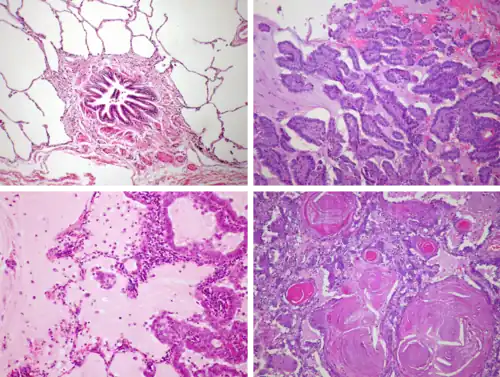

Classification

At diagnosis, lung cancer is classified based on the type of cells the tumor is derived from; tumors derived from different cells progress and respond to treatment differently. There are two main types of lung cancer, categorized by the size and appearance of the malignant cells seen by a histopathologist under a microscope: small cell lung cancer (SCLC; 15% of cases) and non-small-cell lung cancer (NSCLC; 85% of cases).[19] SCLC tumors are often found near the center of the lungs, in the major airways.[20] Their cells appear small with ill-defined boundaries, not much cytoplasm, many mitochondria, and have distinctive nuclei with granular-looking chromatin and no visible nucleoli.[21] NSCLCs comprise a group of three cancer types: adenocarcinoma, squamous-cell carcinoma, and large-cell carcinoma.[21] Nearly 40% of lung cancers are adenocarcinomas.[22] Their cells grow in three-dimensional clumps, resemble glandular cells, and may produce mucin.[21] About 30% of lung cancers are squamous-cell carcinomas. They typically occur close to large airways.[22] The tumors consist of sheets of cells, with layers of keratin.[21] A hollow cavity and associated cell death are commonly found at the center of the tumor.[22] Less than 10% of lung cancers are large-cell carcinomas,[21] so named because the cells are large, with excess cytoplasm, large nuclei, and conspicuous nucleoli.[22] Around 10% of lung cancers are rarer types.[21] These include mixes of the above subtypes like adenosquamous carcinoma, and rare subtypes such as carcinoid tumors, and sarcomatoid carcinomas.[22]

Several lung cancer types are subclassified based on the growth characteristics of the cancer cells. Adenocarcinomas are classified as lepidic (growing along the surface of intact alveolar walls),[23] acinar and papillary, or micropapillary and solid pattern. Lepidic adenocarcinomas tend to be least aggressive, while micropapillary and solid pattern adenocarcinomas are most aggressive.[24]

In addition to examining cell morphology, biopsies are often stained by immunohistochemistry to confirm lung cancer classification. SCLCs bear the markers of neuroendocrine cells, such as chromogranin, synaptophysin, and CD56.[25] Adenocarcinomas tend to express Napsin-A and TTF-1; squamous cell carcinomas lack Napsin-A and TTF-1, but express p63 and its cancer-specific isoform p40.[21] CK7 and CK20 are also commonly used to differentiate lung cancers. CK20 is found in several cancers, but typically absent from lung cancer. CK7 is present in many lung cancers, but absent from squamous cell carcinomas.[26]